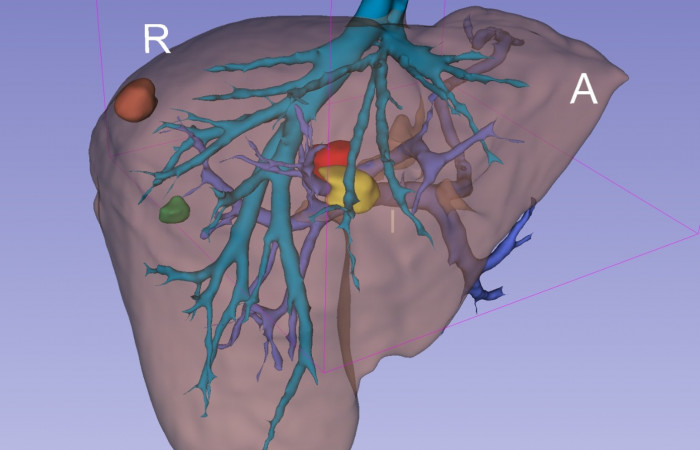

Pracownia Funkcjonalnego i Wirtualnego Medycznego Obrazowania 3D (Pracownia 3D-FM) funkcjonuje w strukturze Zakładu Diagnostyki Obrazowej Szpitala Uniwersyteckiego w Krakowie pod kierownictwem Prof. dr hab. Tadeusza Popieli. Jej celem jest opracowanie i wdrożenie innowacyjnych metod przetwarzania oraz analizy sygnałów i obrazów medycznych, w tym wykorzystanie technologii rzeczywistości wirtualnej oraz metod obrazowania funkcjonalnego. Rozwiązania te wspierają przedoperacyjne planowanie, monitorowanie procedur medycznych oraz wzbogacają proces diagnostyczny o nowe formy wizualizacji danych medycznych.

Zakres działalności

Pracownia 3D-FM zajmuje się m.in. następującymi obszarami:

- Tworzeniem modeli 3D do celów przedoperacyjnego planowania oraz wizualizacji diagnostycznej.

- Obrazowanie Medyczne 3D

- Segmentacja i analiza danych DICOM

- Rekonstrukcja danych medycznych

- Technologie immersyjne (mieszana, rozszerzona i wirtualna rzeczywistość)

Pracownia Funkcjonalnego i Wirtualnego Medycznego Obrazowania 3D łączy nowoczesne technologie z praktycznym zastosowaniem w diagnostyce i terapii. Dzięki interdyscyplinarnej współpracy oraz zaawansowanym narzędziom badawczym dążymy do podnoszenia standardów opieki medycznej w Szpitalu Uniwersyteckim w Krakowie.